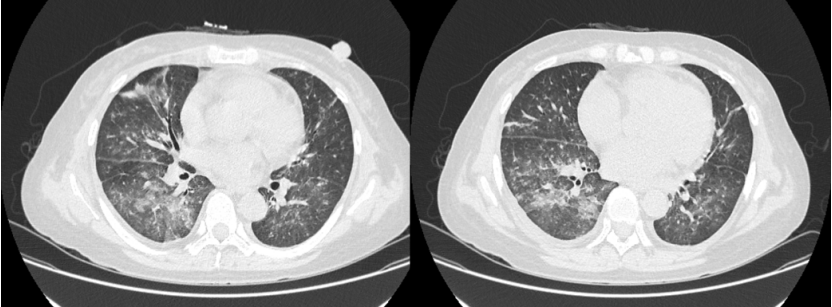

入院当天送KL-6快速进行性升高(图4)患者肺部后续出现机化和纤维化(图5)尽管整个治疗过程非常艰辛但最终预后比较满意。随访胸部CT可见病变吸收良好。

5  患者住院期间胸部CT变化情况